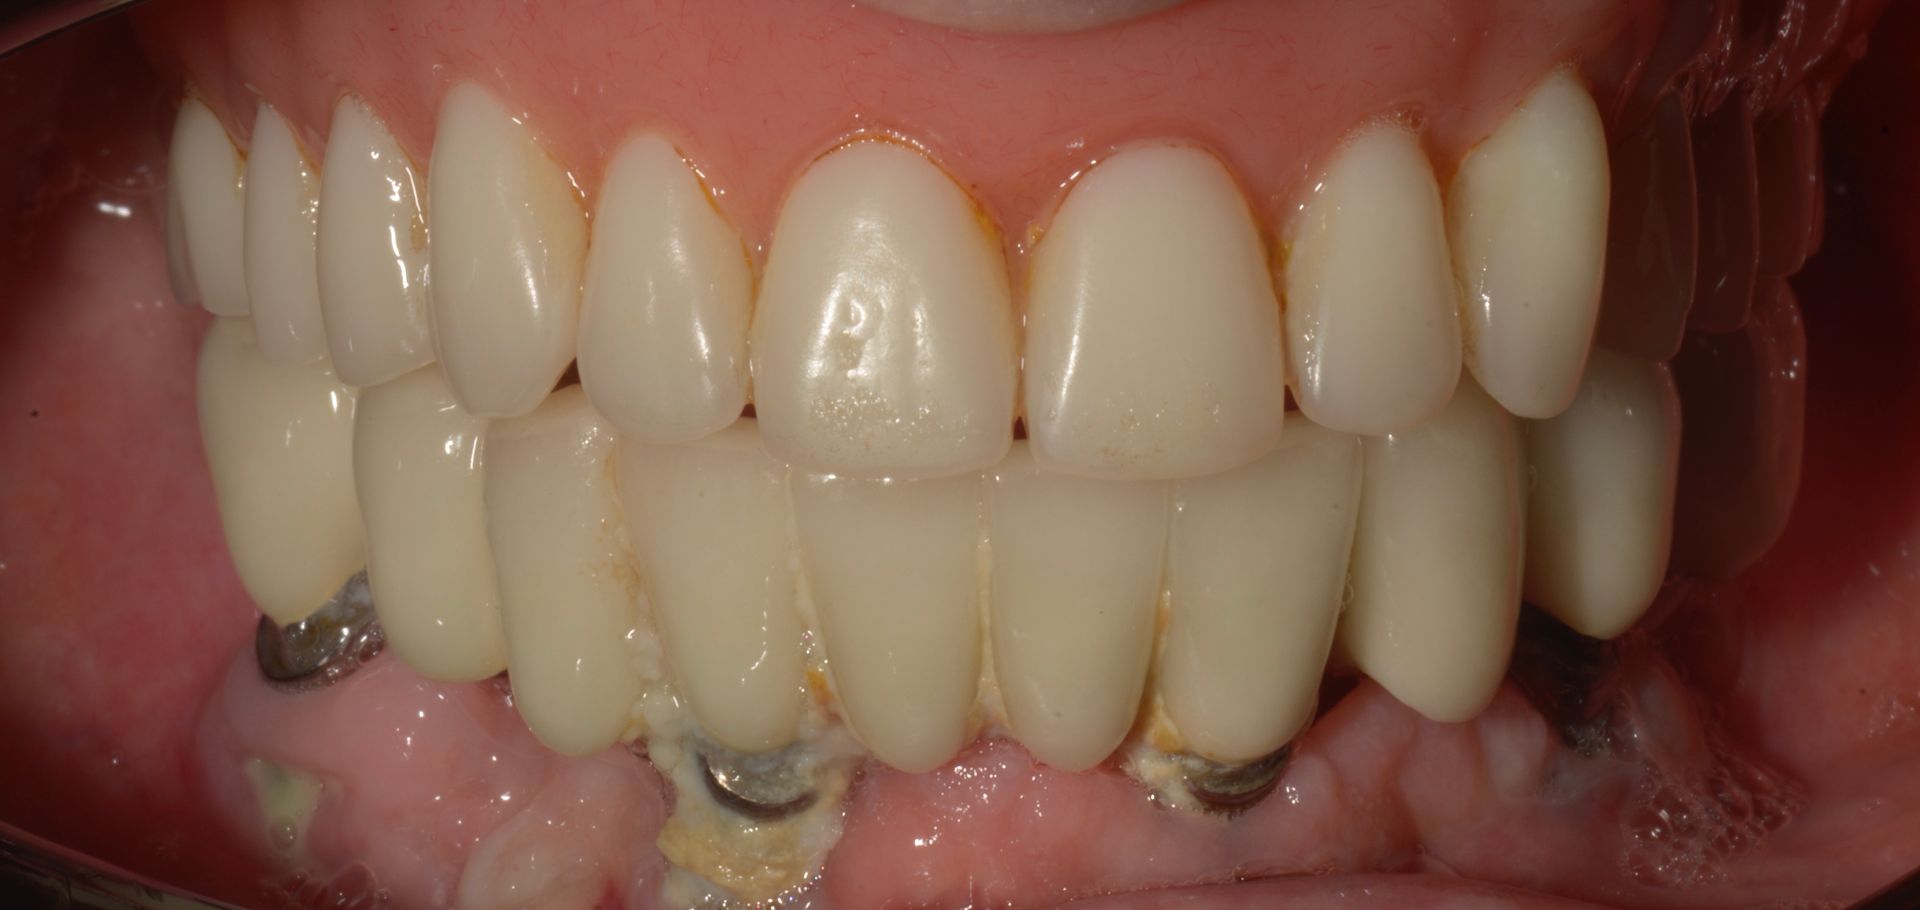

Vedi il caso qui accanto il paziente aveva vecchi impianti falliti e una protesi totale superiore e gli avevano detto che non aveva possibilità di mettere denti fissi...

ecco il caso completo

Il paziente era molto amareggiato perché non tollerava la protesi totale e aveva dolori dovuti agli impianti infetti dell'arcata inferiore. Dopo un attento studio del caso, in cui sono state studiate le forme e le altezze delle nuove protesi e abbiamo eseguito una pianificazione digitale dell'intervento chirurgico impiantare abbiamo inserito 5 impianti nel superiore con una rigenerativa orizzontale e 4 impianti nell'inferiore. a distanza di 4 ore dall'intervento abbiamo caricato gli impianti con le protesi provvisorie a carico immediato fatte con resina e una struttura in titanio, a distanza di 6 mesi sono state sostituite con 2 arcate titanio zirconio.